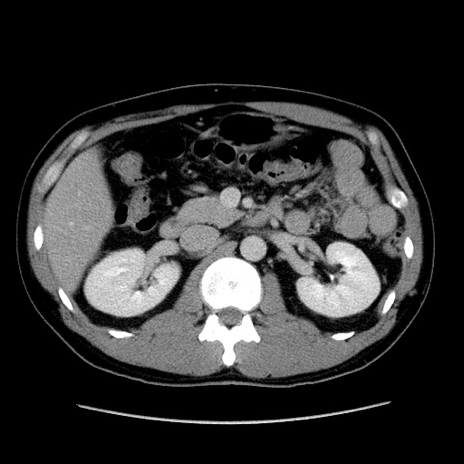

症例4(横断像)

【症例】30歳代男性

【主訴】腹痛、嘔吐

【現病歴】昨晩から突然の腹痛あり、その後嘔吐、軟便も出現。腹痛が改善しないため救急搬送となる。2日前にしめ鯖の食事歴あり。

【身体所見】意識清明、苦悶様、BP 135/90mmHg、BT 35.7℃、腹部:平坦、やや硬、心窩部〜臍部に自発痛、圧痛あり、筋性防御+、反跳痛-

【データ】WBC 8100、CRP 0.57